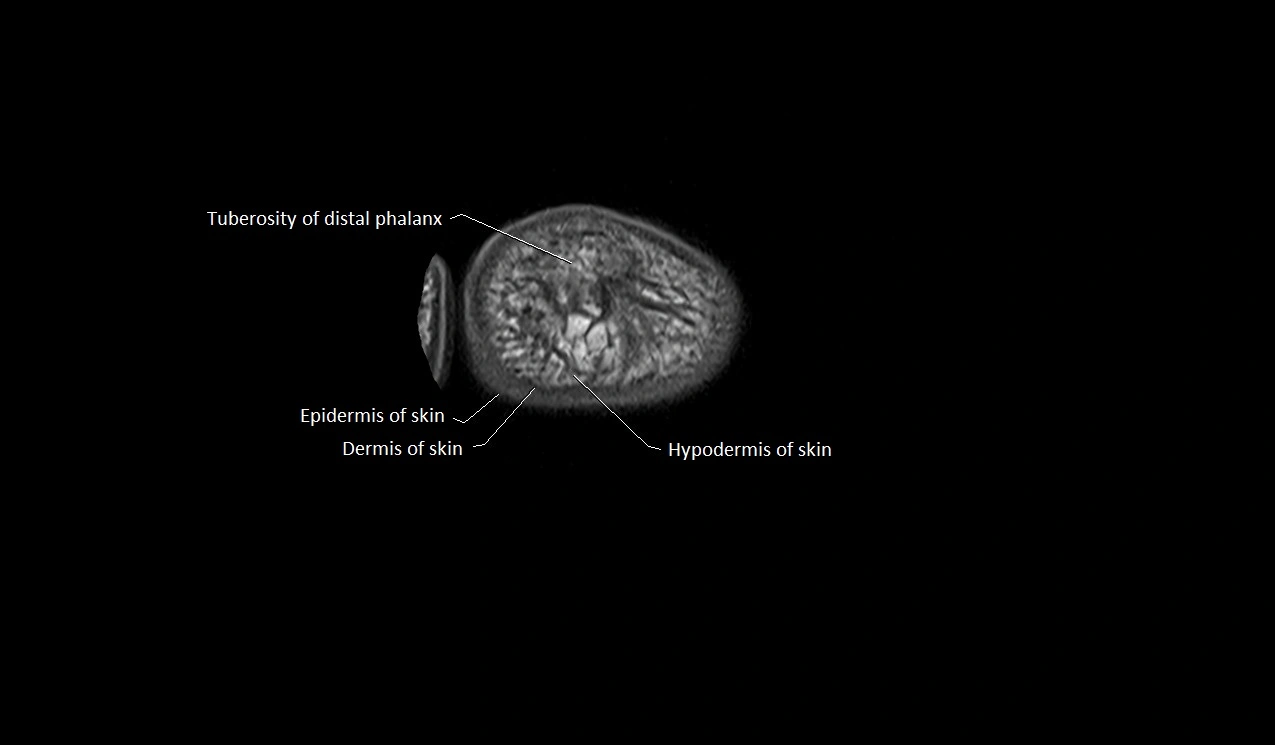

MRI image

image